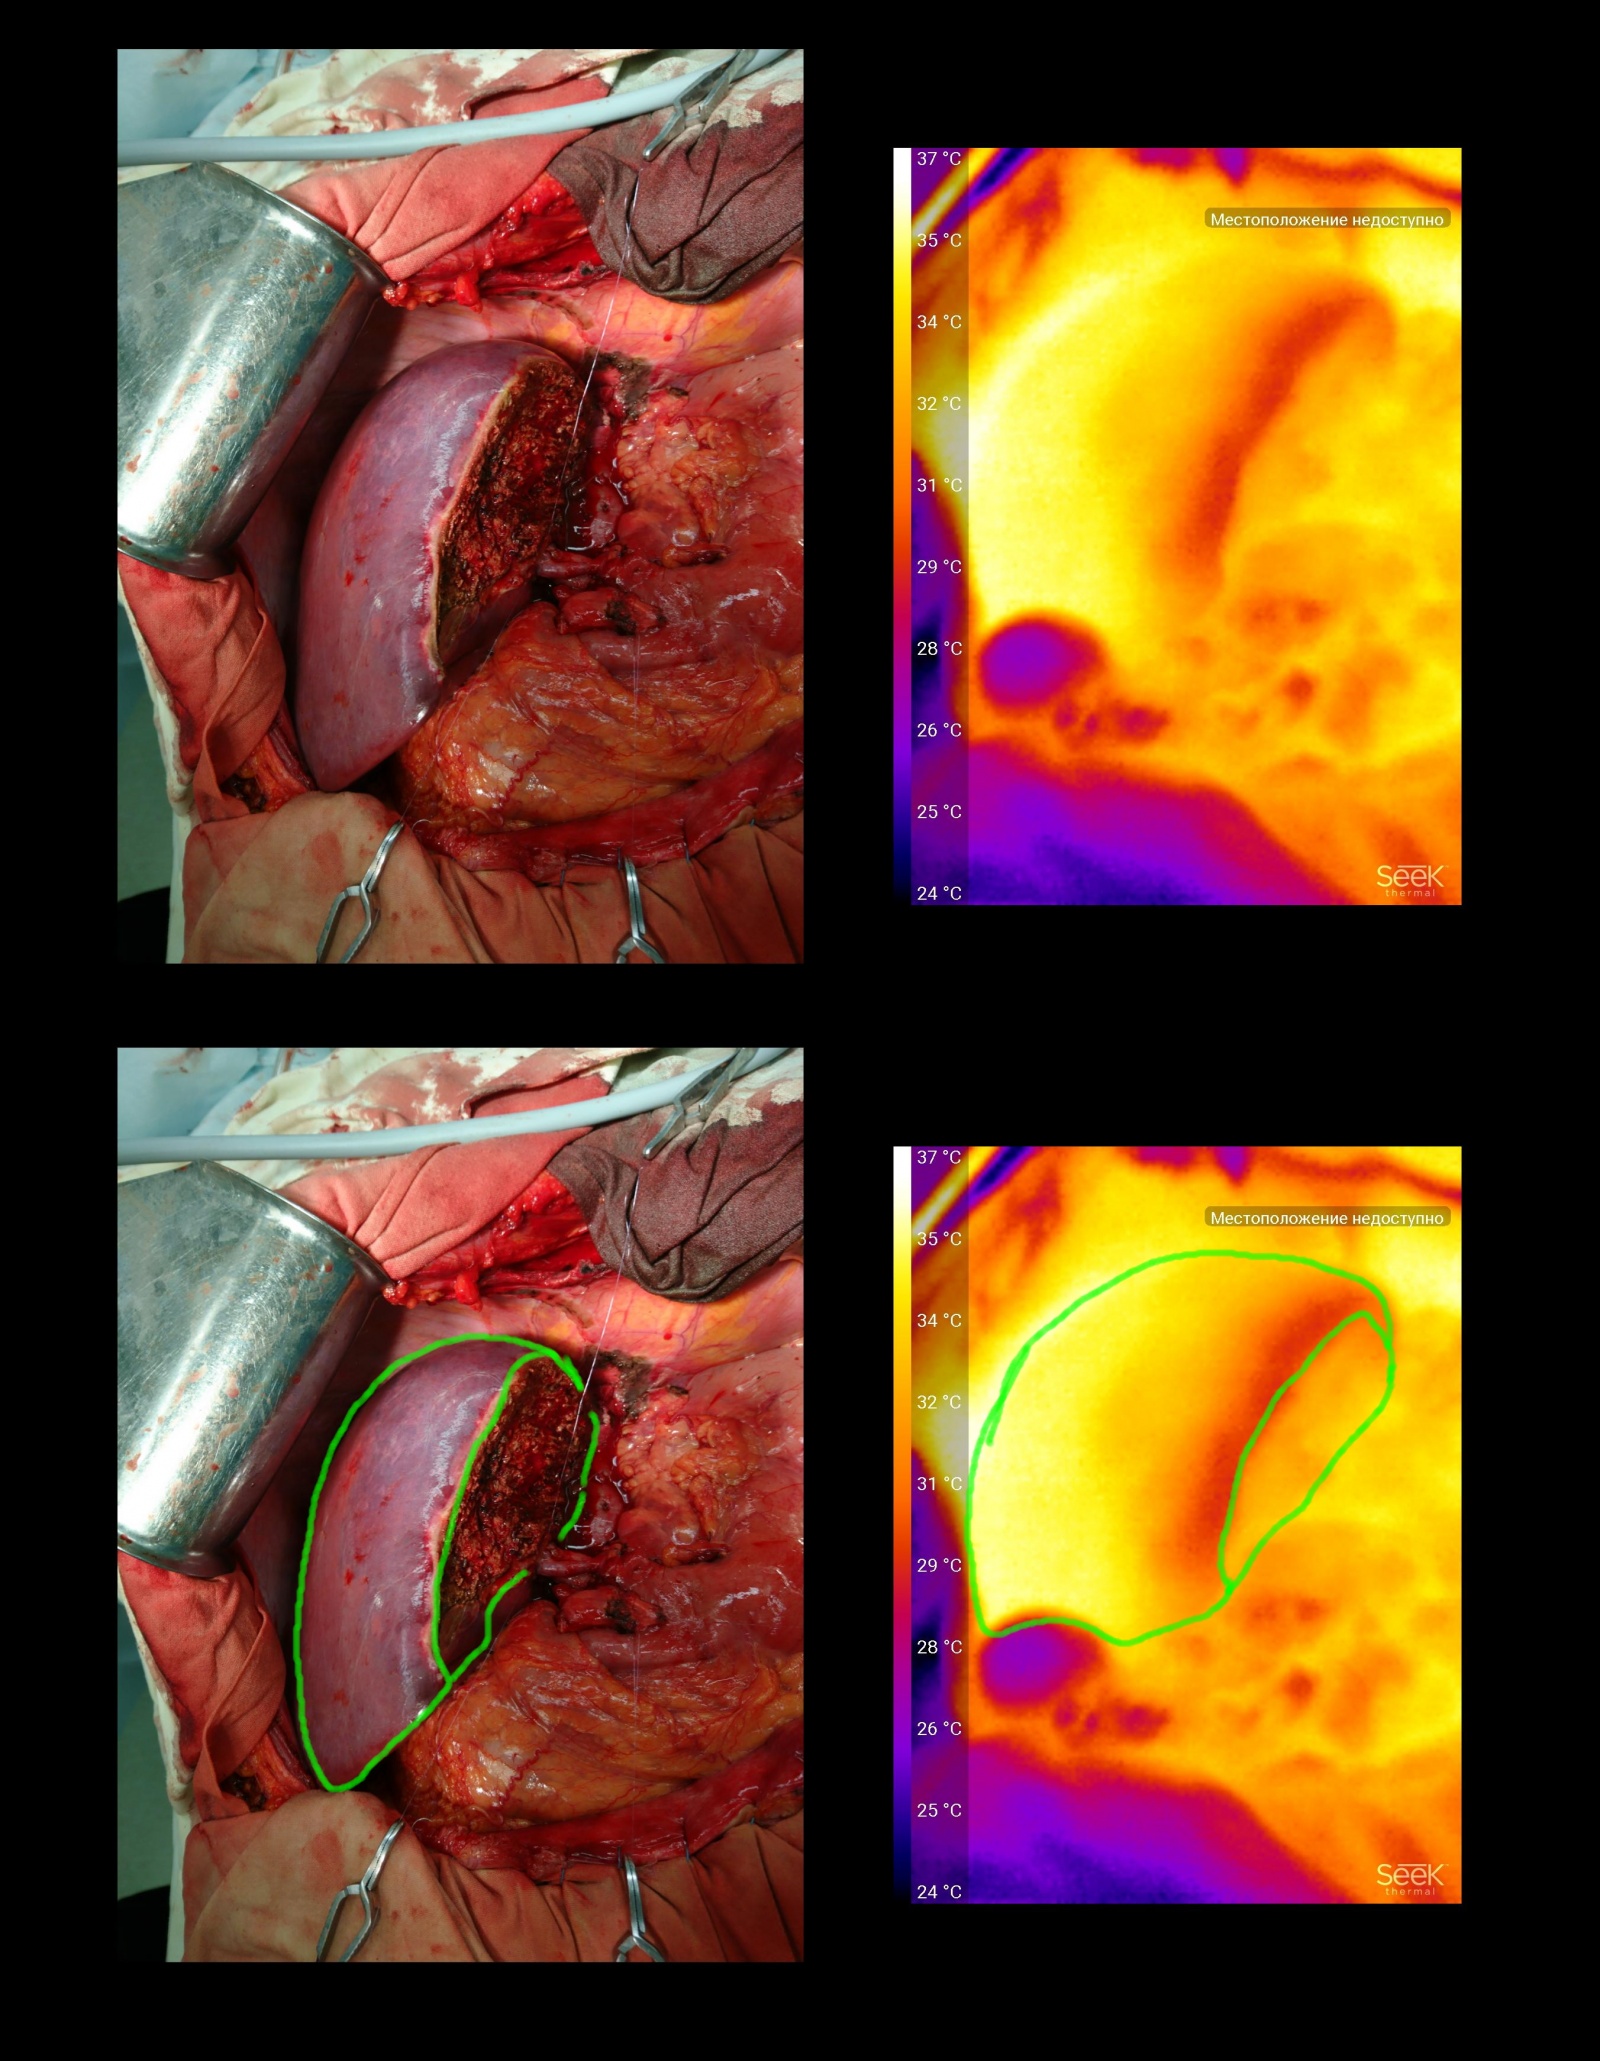

Снимок сделан в ходе операции на желудке. Справа видна оставшаяся часть желудка (обозначено зеленым). Видно, что вся стенка равномерна по температурному сигналу. Фиолетовая полоса (отмечена зеленой штриховкой) соответствует линии резекции сальника — там ткани «запаяны» коагулятором и в будущем сформируют рубец.

Синим выделен зажим, наложенный на двенадцатиперстную кишку. Видно, что ткани выше места пережатия холоднее — в них нет кровотока, они будут удалены в ходе реконструктивного этапа операции.

Другая операция резекции желудка. Цветом обозначен зажим, на котором выходной отдел желудка, отсеченный от двенадцатиперстной кишки. Можно заметить, в отличие от предыдущего примера, что отделы желудка близкие к зажиму более холодные — дело в том, что одна из артерий, кровоснабжающих этот отдел, уже перевязана.